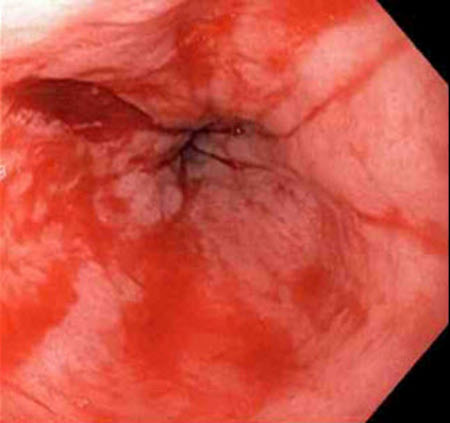

Laceração de Mallory-Weiss: a laceração com sangramento ativo aparece como um defeito longitudinal vermelho com mucosa circundante normal

Do acervo de Juan Carlos Munoz, MD, University of Florida